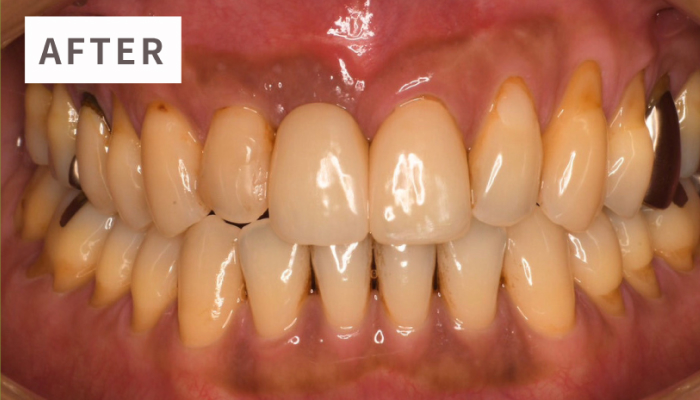

歯がボロボロになっている

長年の治療を繰り返した結果、噛み合わせが崩壊している。

多くの患者様が「なぜこんなに歯が悪くなるのか分からない」と悩みを抱えて当院を訪れます。歯周病インプラント治療を専門に行う私たちは患者様一人ひとりのお口全体を丁寧に診断し、トータルで健康な噛む力を取り戻す治療を提供致します。